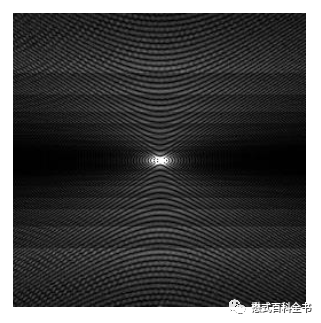

K空间或者原始数据

在判断或者识别伪影的分析过程中,除了通过图像判断,一般还可以根据K空间或者原始数据来判断。这是因为任何磁共振图像都是来源于K空间数据的重建,所以直接检查K空间数据也是非常好的方法。

图19:正常的K空间(重建的图像没有伪影)

图20:K空间异常(K空间污染)硬件系统,重建图像有伪影